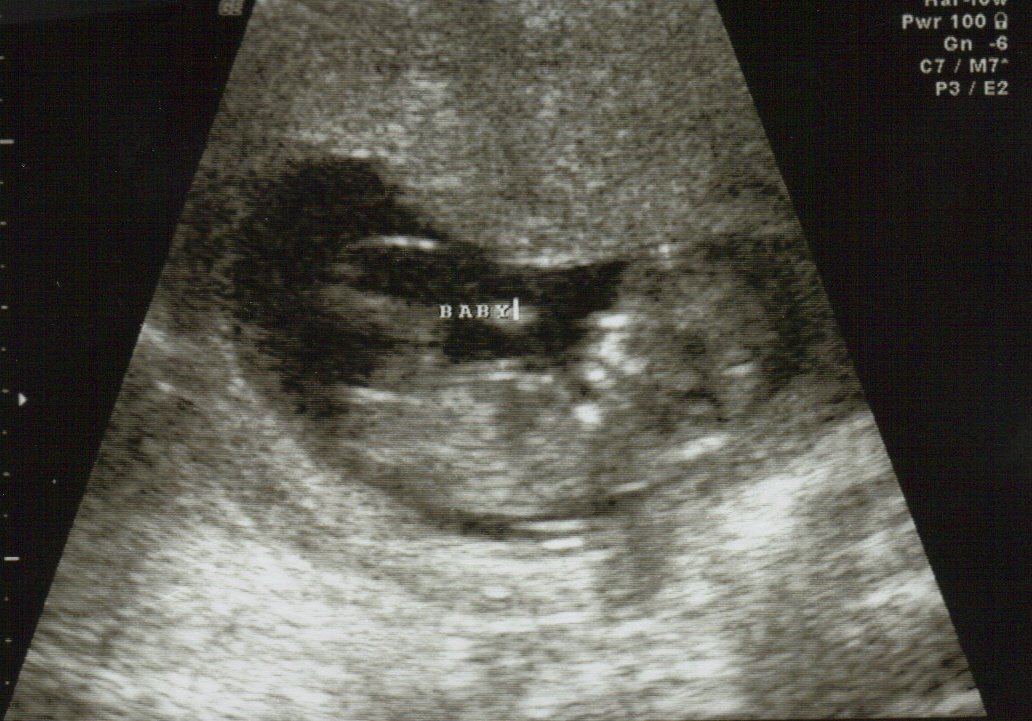

Ultrasound tech said it was a girl at 20 weeks. Just wanted to make sure you guys all agree! Can I buy pink? :babyf:

The baby was measuring 12+1, my dates it was 11 +6. It didn't scan very well. I would LOVE to hear any guesses. I didn't ask the tech, I was just worried about everything being ok with the baby. Thanks for your help!